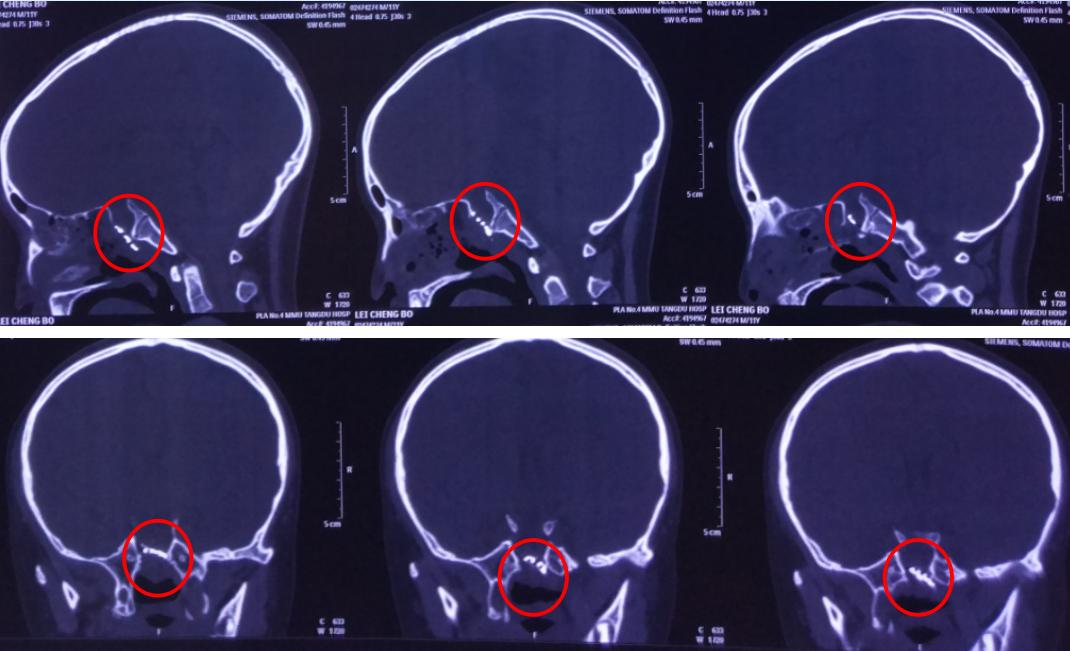

术后影像